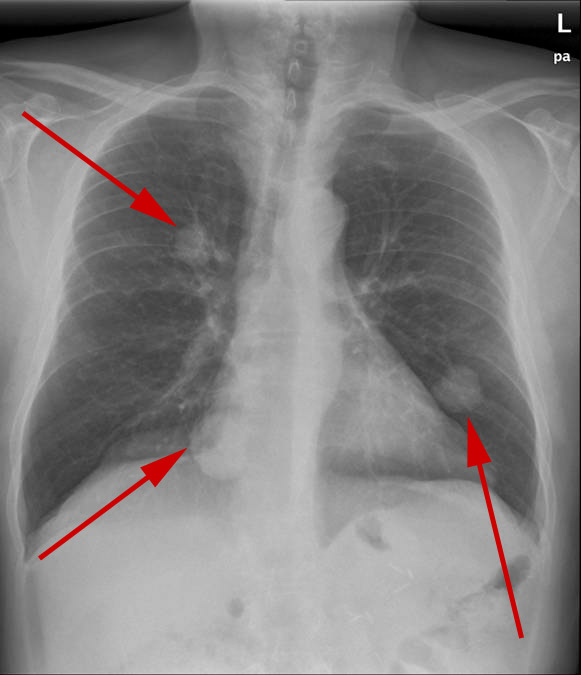

Samme patient som ovenstående - sidebillede.